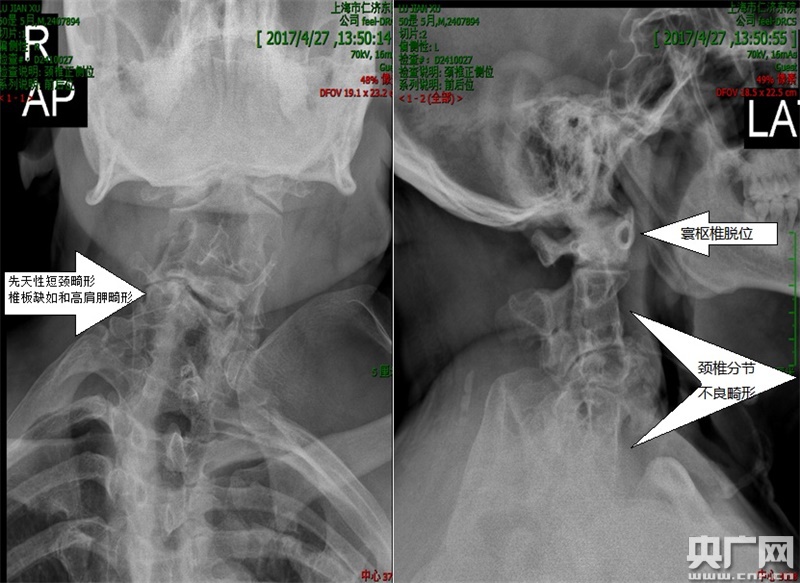

術(shù)前頸椎正側(cè)位X片,正位可見先天性短頸畸形、椎板缺如和高肩胛畸形,側(cè)位可見寰樞椎脫位、頸椎分節(jié)不良畸形。